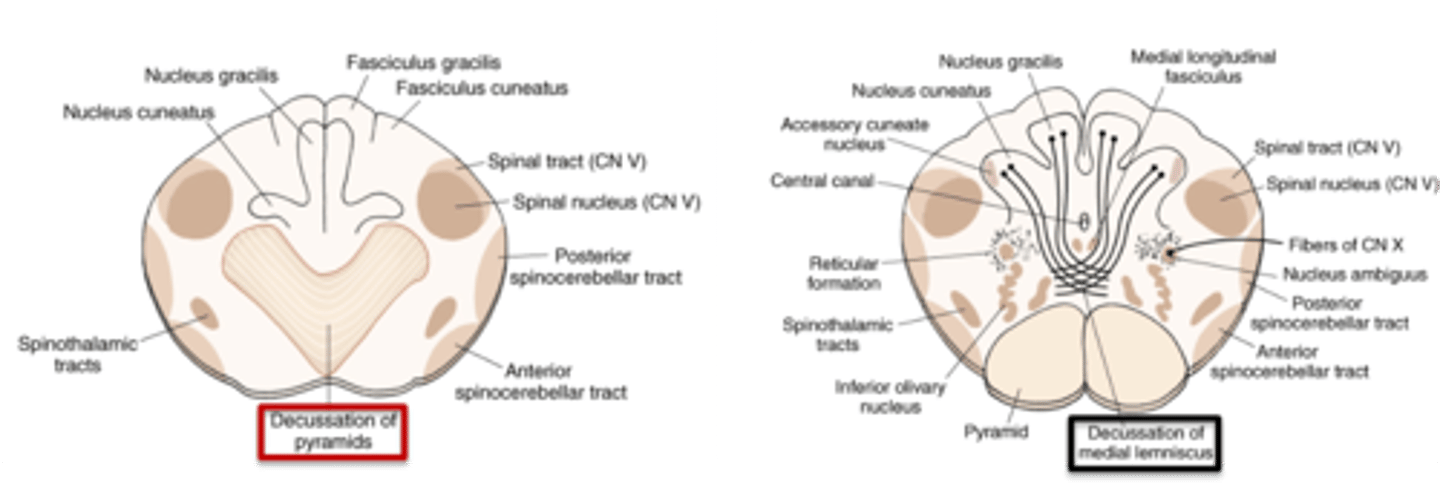

what region of the brainstem contains a motor (pyramidal) and sensory decussation?

medulla

which decussation of the medulla is the site of crossing of corticospinal fibers at the spinomedullary junction? what does it look like?

motor (pyramidal) decussation

looks like a heart <3

which decussation of the medulla is the site of crossing of the dorsal column-medial lemniscus fibers (DC/ML) in the caudal medulla?

sensory decussation